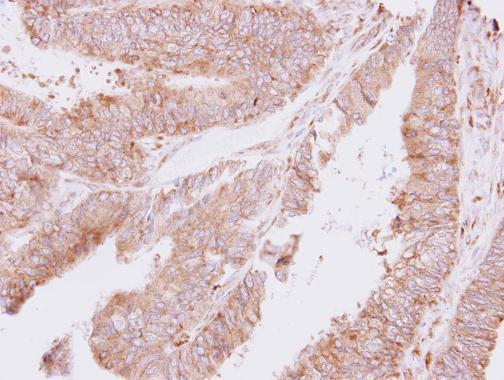

Supportive validation

- Submitted by

- GeneTex (provider)

- Main image

- Experimental details

- Immunohistochemical analysis of paraffin-embedded human colon carcinoma, using ThrRS(GTX109743) antibody at 1:500 dilution.